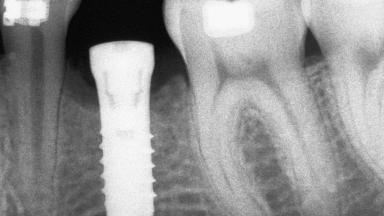

Autologous Block Graft and Guided Bone Regeneration (GBR) for Horizontal Ridge Augmentation in the Posterior Mandible

An 18-year-old man was referred for implant therapy in the posterior mandible to the Department of Oral Surgery and Stomatology (University of Bern, Switzerland). He was healthy and did not smoke. Tooth 35 was congenitally missing, involving a single-tooth edentulous space that offered an adequate mesiodistal dimension for implant placement but exhibited a typical pattern of buccal flattening. A panoramic radiograph was obtained, which revealed a sufficient vertical bone height above the mandibular canal and a normal bone structure in the edentulous area.